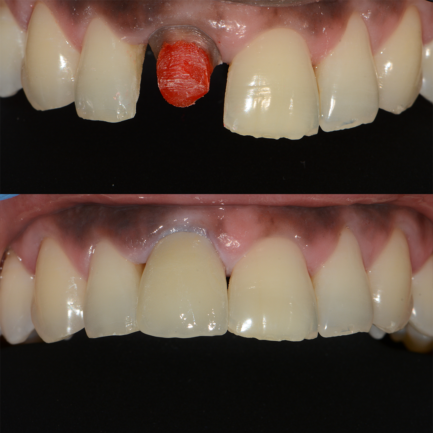

1)Restauration sur dent vivante

Le chirurgien dentiste n’enlève pas le ou les différents nerfs de la dent.

Il procède au nettoyage de la carie avec ou sans anesthésie locale. Une fois cela réalisé le clinicien place directement un composite ou un verre ionomère dans la cavité ainsi nettoyée.

Ce sont des résines blanches esthétiques, tout se fait dans la même séance.

Pour des caries plus profondes ou délabrantes

le chirurgien dentiste fait confectionner des inlays ou onlays en céramique ou en or.

Une prise d’empreinte des dents est réalisée au cours de la première séance, le prothésiste dentaire fabrique à partir des empreintes la prothèse (inlay ou onlay) que le dentiste

placera dans la dent au cours d’un deuxième rendez-vous.

Dans notre cabinet dentaire les inlays ou onlays en or ou en céramique sont préférés aux autres matériaux,

Donc que ce soit pour un composite,un verre ionomère ou un inlay-onlay la dent reste vivante.